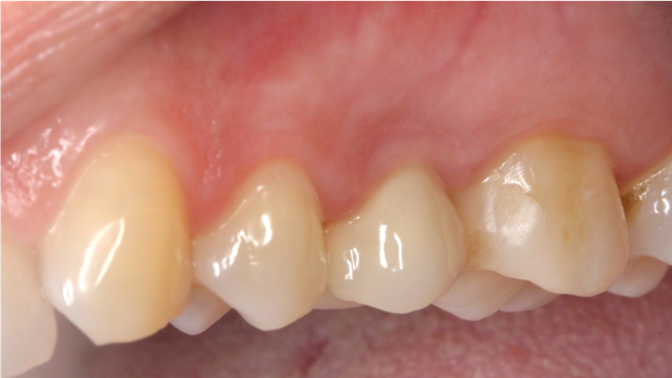

Clinical case: Extraction, immediate implant placement, & provisionalization

- Courtesy of Dr. Iulian Filipov, Romania -

Keywords

AnyRidge, R2GATE, guided surgery, immediate placement, immediate provisionalization, initial stability, Dr. Iulian Filipov, #25, maxillary posterior, immediate loading, Mega ISQ

Products:

AnyRidge implant system, R2GATE, MEGA ISQ, Digital prosthesis